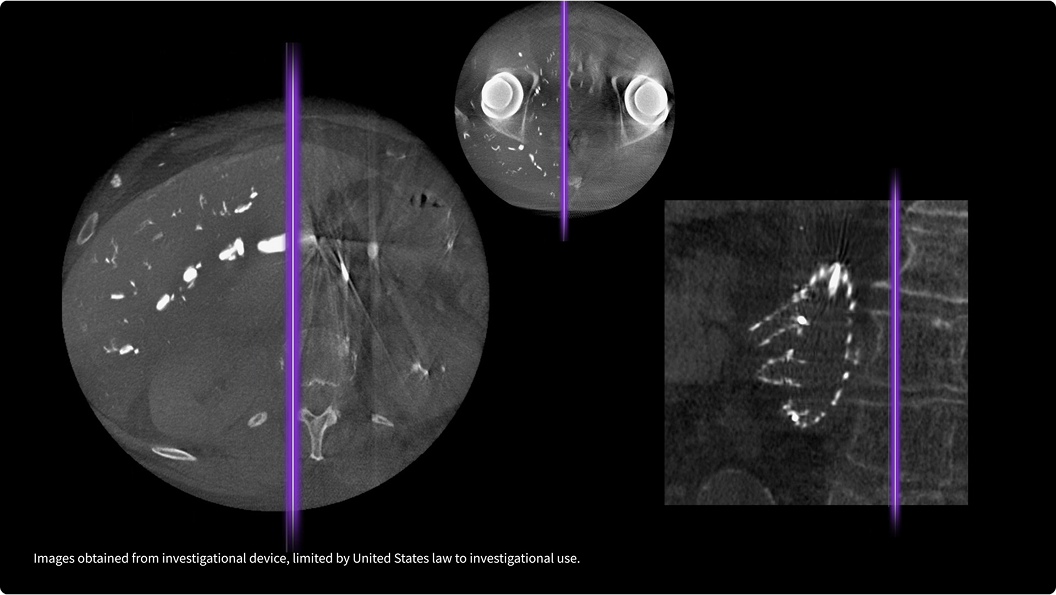

Качество изображений, на которое вы можете положиться

Новый подход к сканированию мочевого пузыря